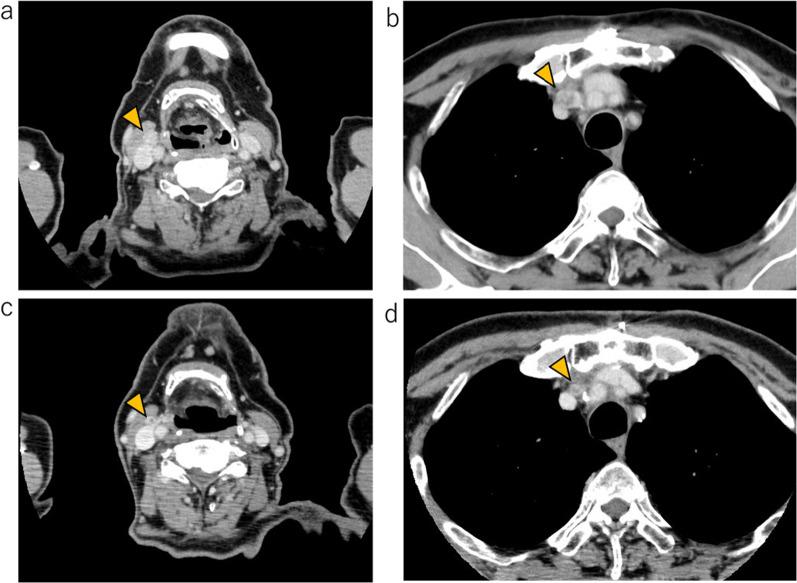

We report a case of MMFCC treated with selpercatinib. The patient was a 69-year-old male presenting with tumors in the right thyroid lobe and in the upper mediastinum. Fine-needle aspiration (FNA) cytology of the right thyroid lobe tumor revealed a medullary carcinoma; germline RET mutations were not detected. After resection of the right thyroid lobe with central node dissection, rapid intraoperative diagnosis of the mediastinal mass confirmed malignancy, leading to total thyroidectomy with excision of the upper mediastinal tumor. Histologically, the tumor in the right thyroid lobe and the pretracheal lymph node revealed a mixture of medullary and follicular carcinoma components, diagnosed as MMFCC. The mediastinal lymph node exhibited only medullary carcinoma components. At 11 months postoperatively, computed tomography scans showed enlargement of the right supraclavicular and upper mediastinal lymph nodes. FNA cytology of the right supraclavicular lymph node suggested the recurrence of medullary thyroid carcinoma. The gene panel testing (The Oncomine Dx Target Test Multi-CDx system®, Thermo Fisher SCIENTIFIC) of metastatic lymph node revealed RET somatic mutation (M918T). Treatment with selpercatinib was initiated, and both the cervical and mediastinal lymph nodes showed a reduction in size.

我们报告1例接受塞尔帕替尼治疗的MMFCC患者。该患者为69岁男性,表现为右甲状腺叶及上纵隔肿瘤。右甲状腺叶肿瘤的细针穿刺(FNA)细胞学检查显示为髓样癌;未检测到胚系RET突变。在切除右甲状腺叶并进行中央淋巴结清扫后,术中对纵隔肿块的快速诊断证实为恶性,遂行全甲状腺切除术并切除上纵隔肿瘤。组织学检查显示,右甲状腺叶和气管前淋巴结的肿瘤呈现髓样癌和滤泡癌成分的混合,诊断为MMFCC。纵隔淋巴结仅表现为髓样癌成分。术后11个月,计算机断层扫描显示右锁骨上和上纵隔淋巴结肿大。右锁骨上淋巴结的FNA细胞学检查提示甲状腺髓样癌复发。转移淋巴结的基因检测(Oncomine Dx Target Test Multi-CDx系统,赛默飞世尔科技公司)显示RET体细胞突变(M918T)。开始使用塞尔帕替尼治疗后,颈部和纵隔淋巴结均缩小。